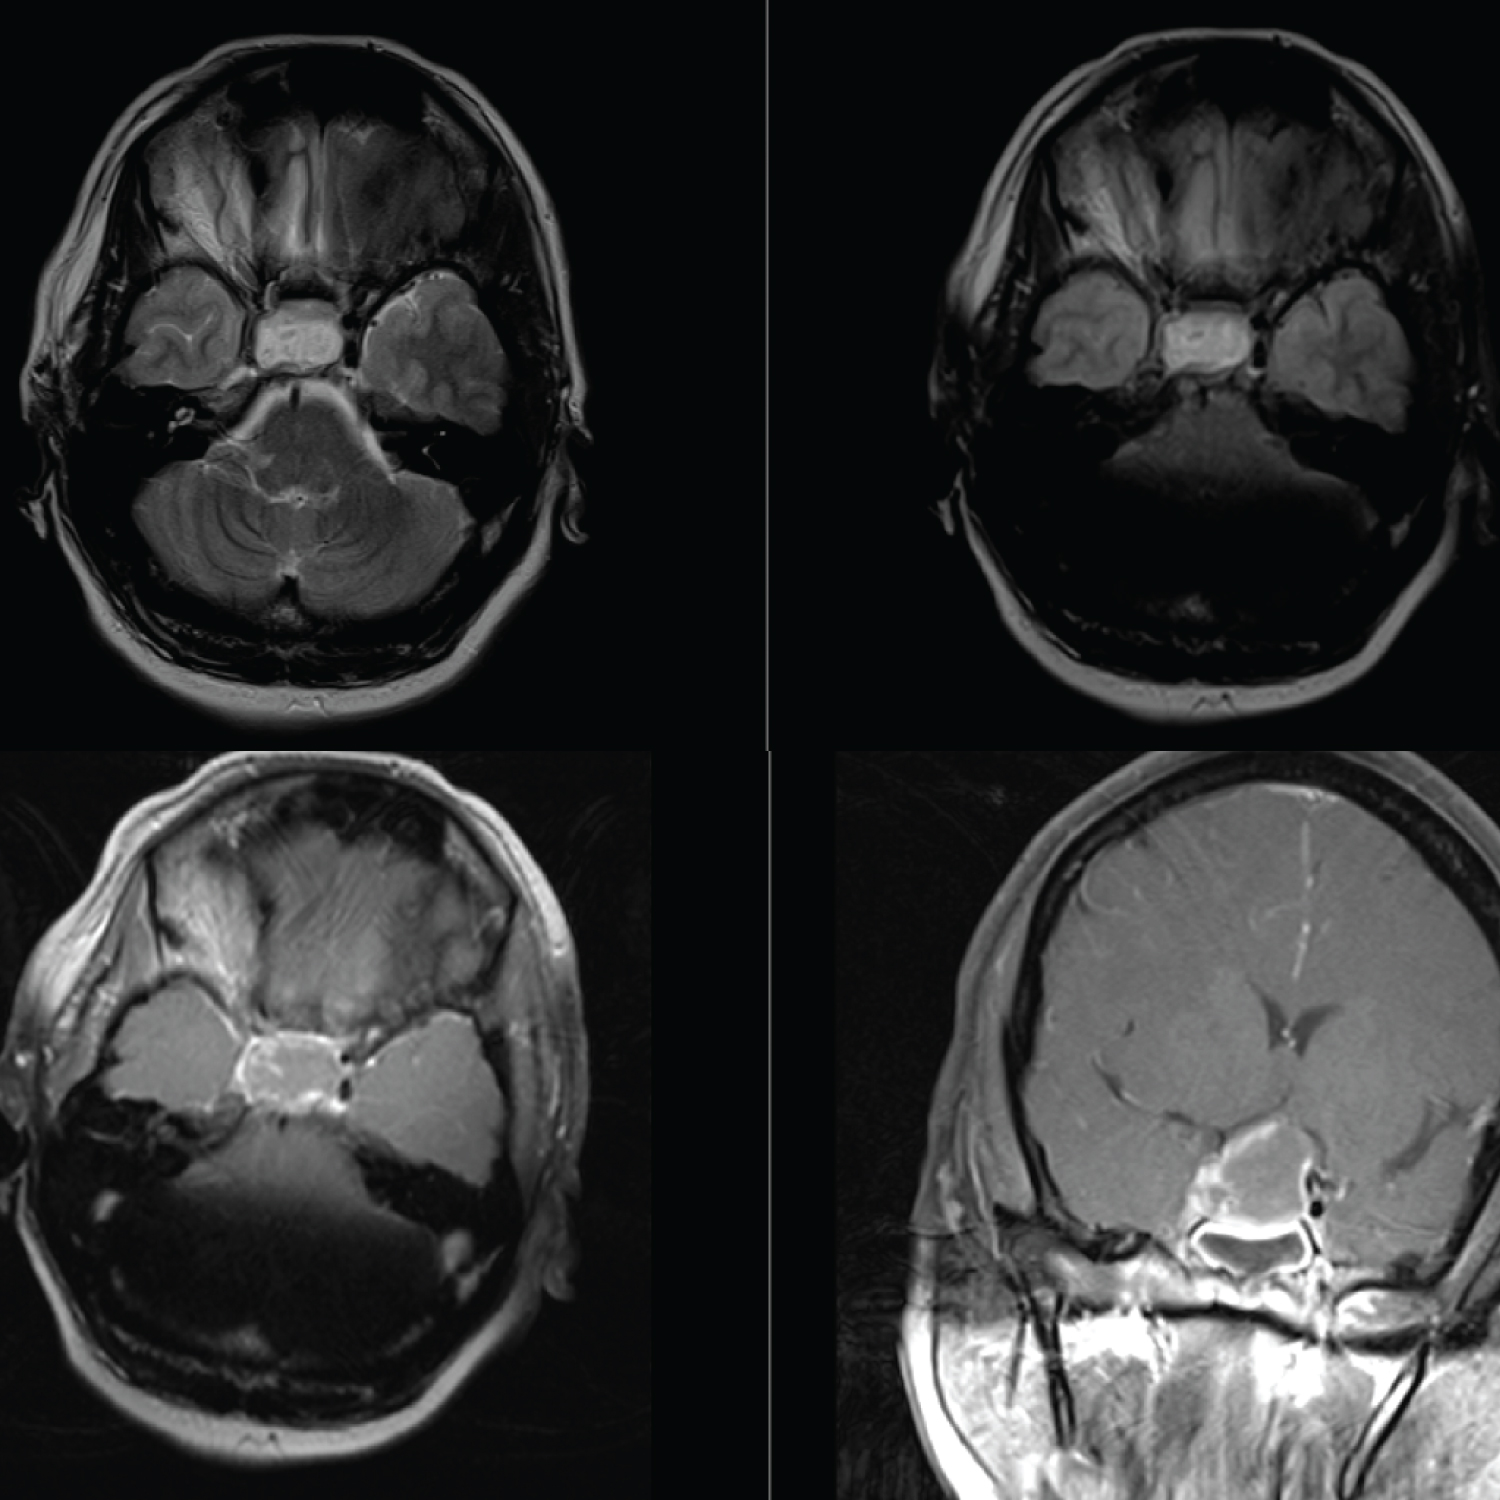

CT scan of the brain showed a hypodense region in the territory of the right ACA and MCA, consistent with an acute ischemic infarct (Figure 1), but no significant mass effect or midline shift. A hyperdense mass was noted in the region of the pituitary fossa, suspicious for a hemorrhage in a pituitary adenoma. The patient had an urgent MRI/MRA of the brain, which revealedanapoplectic grade 3 pituitary adenoma. There was compression of the cavernous segment of the right ICA (Figure 2), which was the likely culprit for her ischaemic infarct.

Figure 2: Top left: T2 weighted axial image showing heterogenous signal intensity within the sella with right lateral extension into the cavernous sinus and compression at the supraclinoid segment of the right ICA; Top right: T1 pre contrast image showing high signal intensity within the pituitary gland suggesting an apoplexy. Bottom left and right: Axial and Coronal planes of T1 post contrast images showing a large ovoid mass with minimal enhancement with expansion into the suprasellar cistern displacing the optic chiasma minimally. The apoplectic adenoma is expanding laterally into the cavernous sinus with direct compression at the supraclinoid segment of the right. View Figure 2

In our case, there was radiological evidence of intratumoral hemorrhage resulting in the compression and stenosis of the supraclinoidal segment of the right ICA due to mechanical forces exerted on the vessel (Figure 2). This resulted in the right-sided anterior circulation cerebral infarct and left hemiplegia. Rapid expansion from the hemorrhage results in raised intrasellar pressure of up to 58 mmHg in PA. This results in lateral displacement of the adenoma into the cavernous sinus and subsequent compression of the ICAs which results in the cerebral ischemia [7].